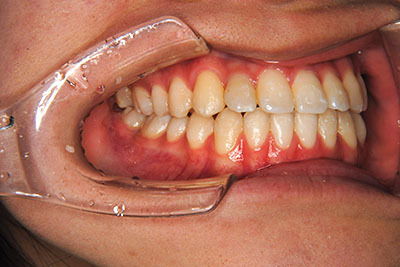

小学生高学年や中高生で矯正治療を考えている方へ

歯が乳歯から永久歯に生え変わった小学生高学年や、中高生でも矯正治療に手遅れということは全くありません。

成長中の顎の骨を矯正できたり、この時期の矯正はおとなになってから矯正治療を始めるよりも短期間で済むことがほとんどです。当院だとおおよそ1年で動的治療(マルチブラケット装置をつける期間)が終わることが多いです。